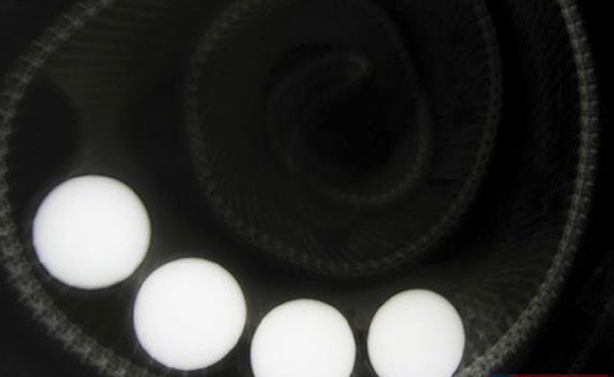

Avusturalya'da yakalanan yaklaşık bir metre uzunluğundaki bu yılan ise yumurta sandığı golf toplarını yuttu.

#47